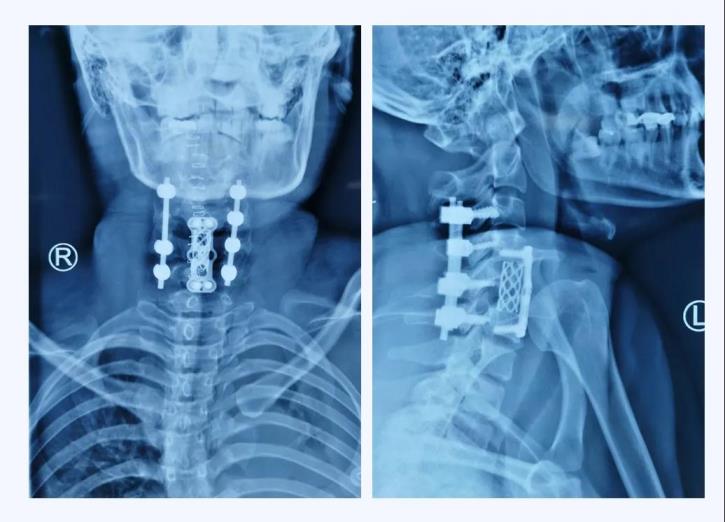

術(shù)后X線(xiàn)

當(dāng)手術(shù)接近尾聲,X線(xiàn)透視機(jī)完美完成術(shù)區(qū)拍攝的一剎那,手術(shù)團(tuán)隊(duì)的所有成員無(wú)不發(fā)出由衷的贊嘆,手術(shù)非常成功!頸椎序列完整的恢復(fù)了!

術(shù)后第一天,患者的左上肢已能離床抬起、右上肢肌力也開(kāi)始恢復(fù)。術(shù)后一周,患者生命體征恢復(fù)正常,肢體功能逐漸恢復(fù)。